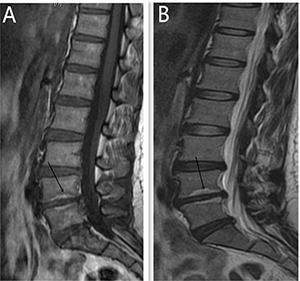

Figure 3: Modic type 2 changes was presented by MR for a 46 year old women, diagnosed with discogenic LBP for 10 months. (A) is High T1 signal (L4-5). (B) indicates High T2 signal (L4-5).

Modic changes appear as the subchondral signal abnormalities on MRI in the bone marrow adjacent to degenerated discs, and it has also be confirmed to be associated with discogenic LBP [17–19]. An recent cadaver research showed that bony endplate lesions had association with the history of LBP [20], and both Modic changes and bony endplate defects could contribute to the LBP. Increased signal intensity (SI) of nucleus pulposus and an accelerated process of disc degeneration have also been confirmed in the process of Modic changes [21–22]. More patients in the symptomatic group own Modic change when compared with the control group (I,17 vs 5; II,31vs 0;III,7 vs 0; P = 0.00) based on the results of the univariate analysis. Modic changes can also applied to forecast the discogenic LBP and show high diagnostic significance according to the results of multivariate analysis (p = 0.017) and ROC curve (AUC = 0.747). The results conducted by our research confirmed the association between the discogenic LBP and Modic change.

Angle motion of the lumbar spine intervertebral was measured to indicate the degree of spine instability and include angle motion and lumbar mobility [32].Two lines across the upper and lower vertebral body margin of lesion level insect and form the angle at flexion and extension position by X-ray (Phillips,Eindhoven, Netherlands), difference of the flexion and extension angle was defined as the angle motion of lumbar spine [33]. Lumbar mobility was measured by calculating the distance between upper and lower vertebral body of the lesion level at the lateral position by X-ray. The cobb angle of interest is simply the angle between the two line drew from the upper endplate of the upper body and along the lower endplate of the lower body [34]. Height of the lesion disc was measured by supine MR (Siemens,Germany). The T1 and T2 intensity images were constructed with the TE/TR of 10/500 ms and 100/2800 ms. The slice thickness was 4 mm. We performed the measurement on the T2 intensity images at the sagittal planes. The measurement of the vertical intervertebral disc lengths was performed on the mid-saggital section of the vertebral body (anterior, middle and posterior). Measurement of spinal canal dimensions of the lesion level (saggital diameter and transverse diameter) was carried out by supine MR to reflect degree of the lumbar spinal stenosis [35]. HIZ was defined as a small, round zone with limited high-intensity signals in the posterior annulus of lumbar intervertebral discs on sagittal slices of T2-weighted MR, it also represents a deep radial fissuring the annulus fibrosis of the lesion level, just as revealed by lumbar CT discography [36–39]. Modic changes are usually displayed by MR to describe the signal intensity changes of vertebral end-plate of the lesion disc [40]. Modic type 1 changes (MC1) refers to low T1 and high T2 signal, MC2 refers to high T1 and T2 signal, and MC3 refers to low T1 and T2 signal [41]. Grading of disc degeneration was assessed from T2-weighted sagittal images based on the Pfirrmann method [31]. Two independent spine surgeons performed the measurement by using Centrieity Enterprise Web V3.0 (General Electric,US).